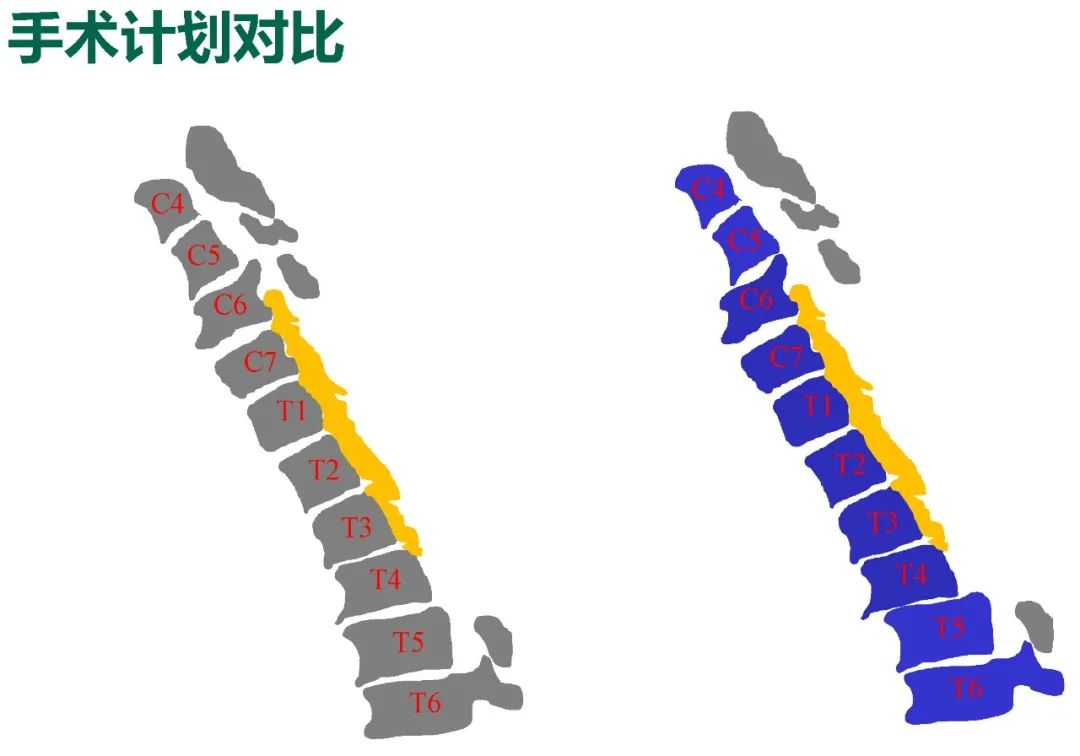

诊断&治疗:

Thoracic spinal stenosis(T2-T3)

Thoracic spinal stenosis decompression(T2-T3)